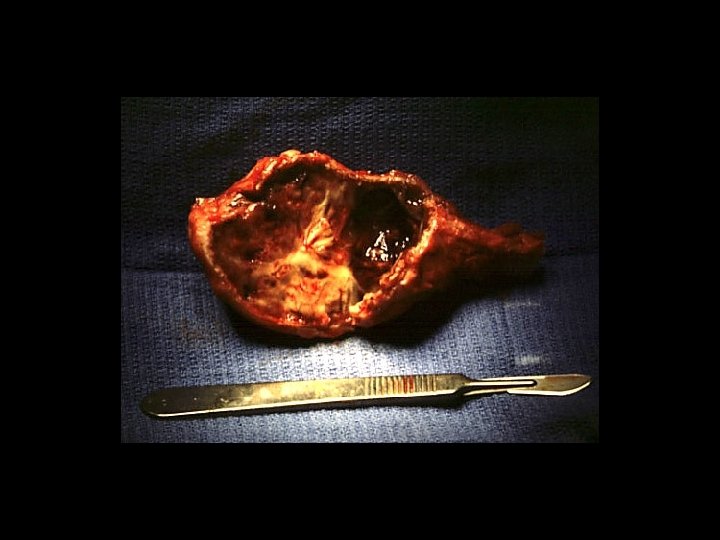

Giant cell tumour • • Uncertain origin Occurs in mature bone Area of old epiphysis Distal femur, proximal tibia, proximal humerus, distal radius.

TREATMENT OPTIONS 1. Curettage & bone graft 2. Curettage & bone cement 3. Excision without replacement 4. Excision & replacement with: Artificial prosthesis (custom made) Allograft 5. Excision & replacement with upper end fibula 6. Excision & arthrodesis